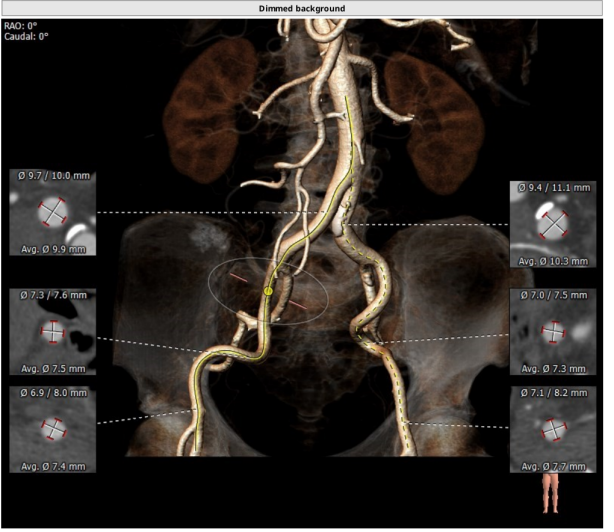

术前CT评估提示

TYPE1型二叶瓣,重度钙化,左右可见钙化融合脊,法式窦结构可,双冠高度可,升主动脉增宽,最宽处约46 mm,心脏角度不大,左室大,心尖部可见囊状造影剂填充,考虑多系小室壁瘤,术中需谨慎操作,主动脉弓部走行较平缓。

瓣环平均直径:21.9 mm,左室流出道平均直径:21.6 mm,钙化积分:865.9 mm³

左冠开口高度:11.8 mm,右冠开口高度:13.4 mm